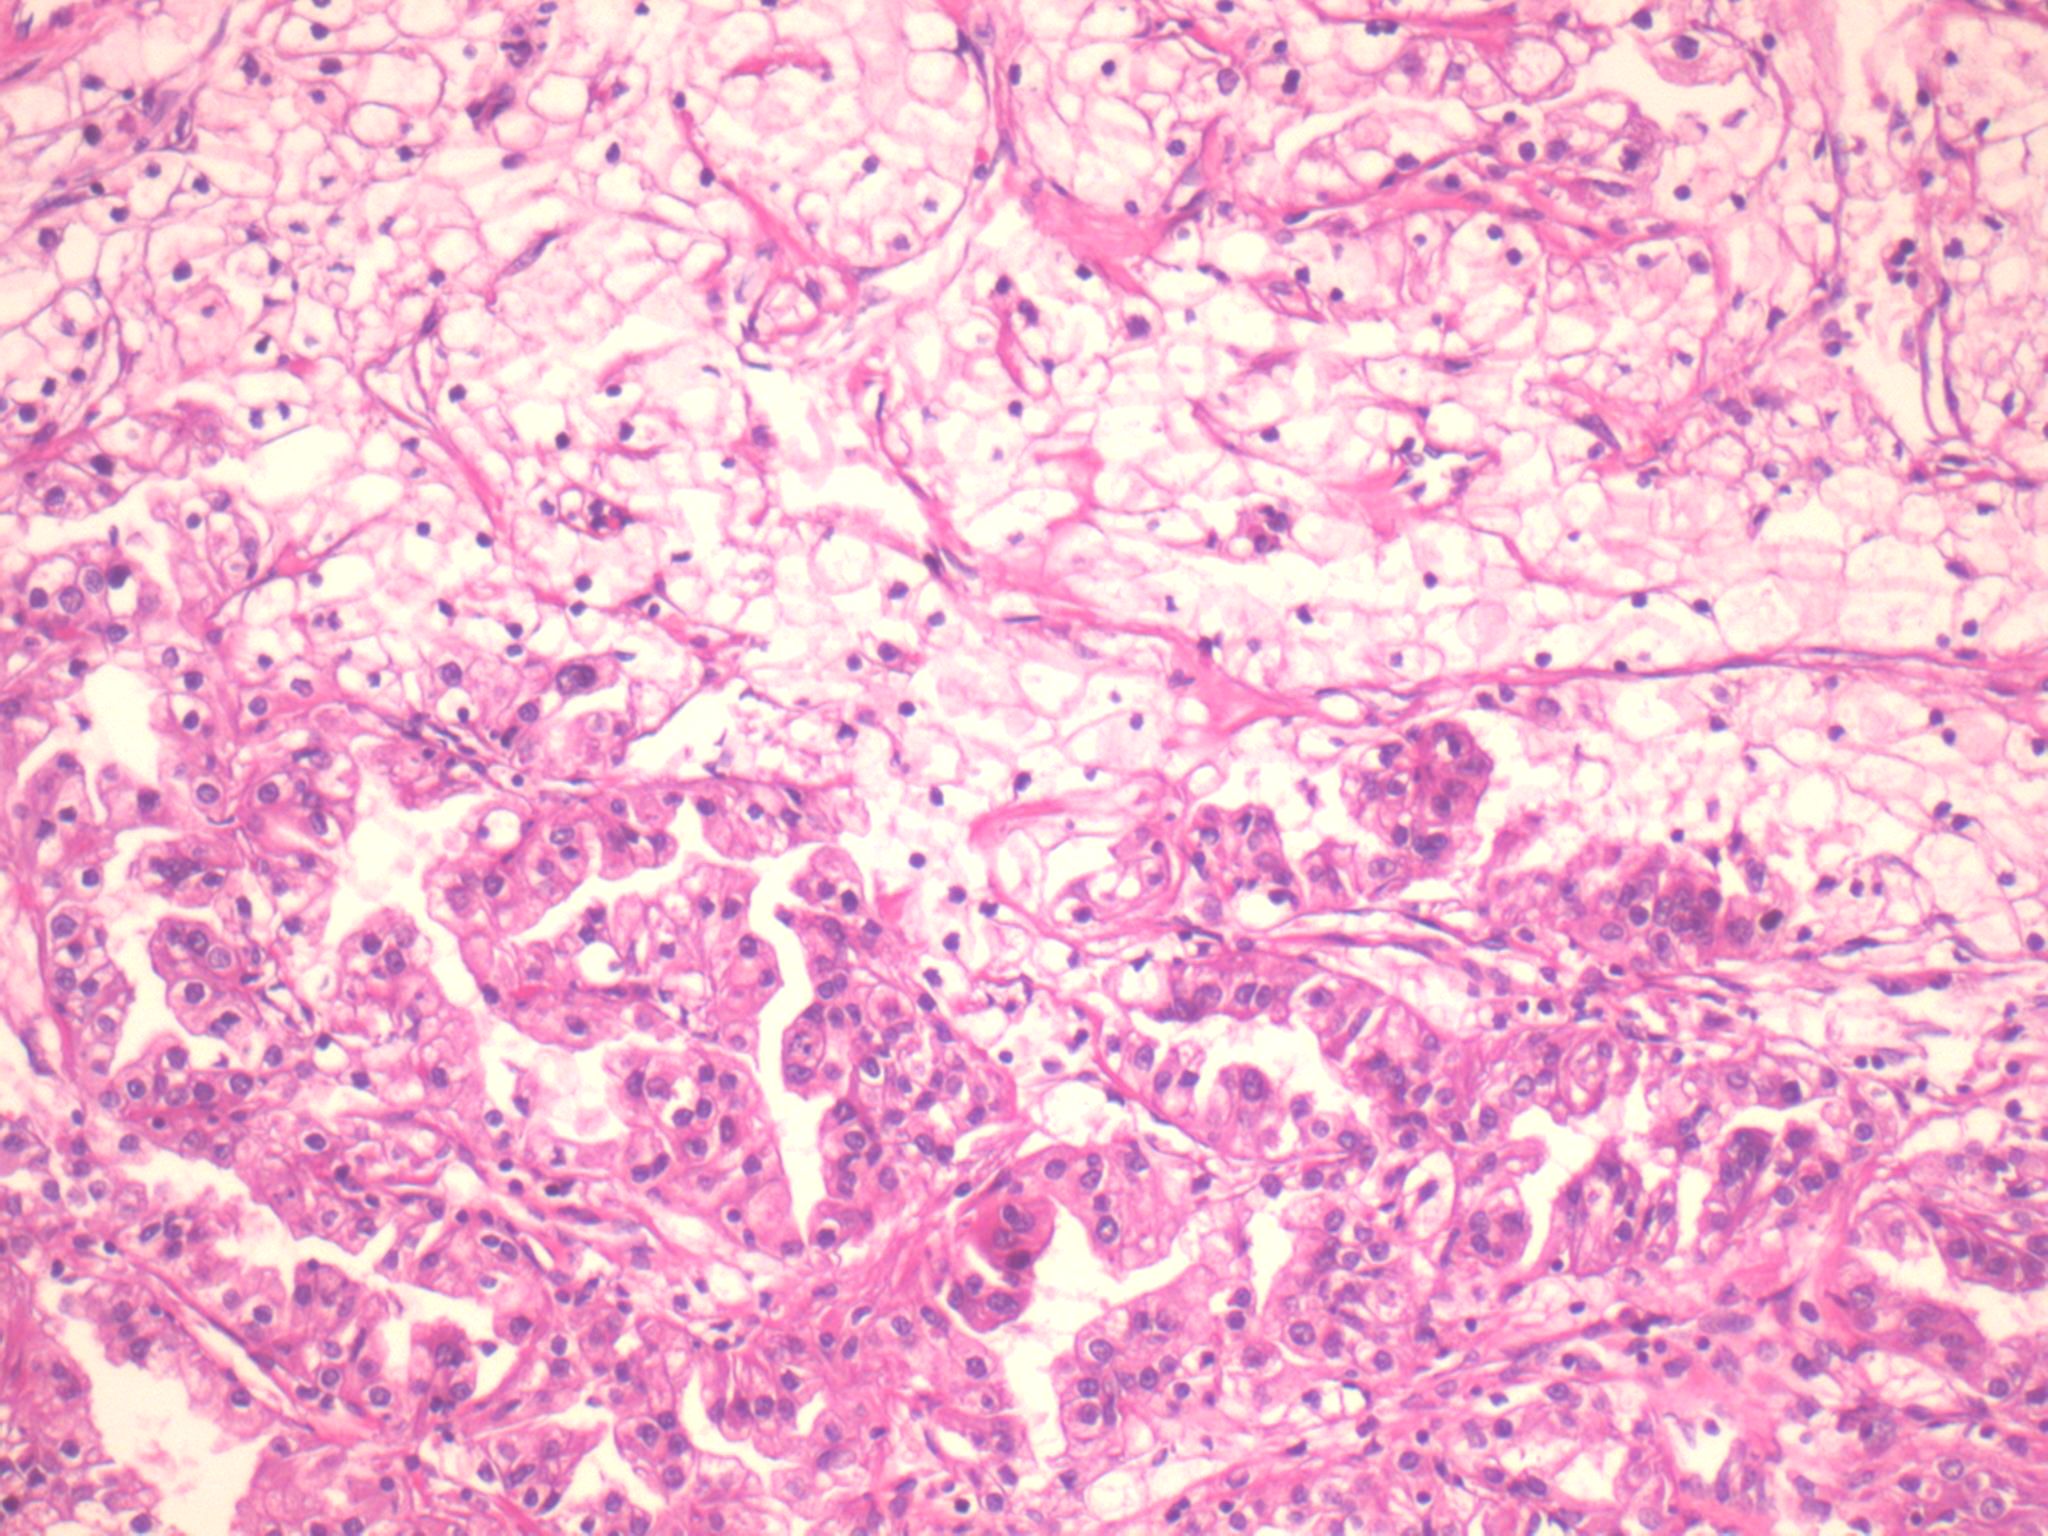

Consensus grade: Clear cell RCC

Neoplasm composed of clear cells